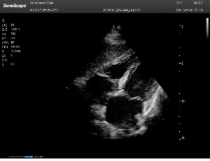

左室長軸

四腔心